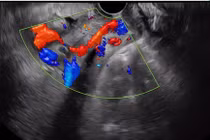

Rau tiền đạo có cài răng lược là một bệnh lý nguy hiểm, có khả năng đe dọa tính mạng mẹ và thai nhi, sản phụ cần chú ý thăm khám và quản lý thai chặt chẽ để phát hiện và xử trí kịp thời.

Rau tiền đạo trung tâm, rau cài răng lược là bệnh lý sản khoa nguy hiểm khi bánh rau đâm xuyên qua lớp cơ tử cung, xuyên thành bàng quang, trực tràng.... Bệnh gây ra nhiều biến chứng nguy hiểm, đe dọa tính mạng cả thai phụ lẫn thai nhi.

Sản phụ đã mổ đẻ 3 lần không chỉ bị rau tiền đạo trung tâm, rau cài răng lược, đa ối mà rau mặt trước lan qua lỗ trong cổ tử cung, đâm xuyên thành bàng quang... đã được cứu sống.